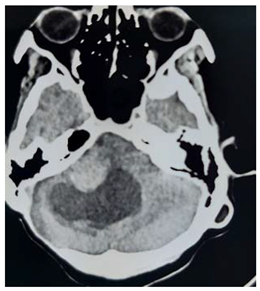

This is 16 years male, off school, experiences history of febrile illness and headache for long duration, presented to neurosurgery emergency unit with convulsions and deterioration level of consciousness this was 4 months before his presentation.

On examination: he was unwell, severe loss of weight, dry skin with multiple café aulate spots all over his body; there was bilateral eye globe proptosis.

Patient was admitted to ER and resuscitation was done

Operation: After clear counseling to the family, subsequently Left fronto –tempro-parietal craniotomy was done, operative findings: very thin bone with multiple eaten parts, the dura was very thin and adherent to the over lining bone, the tumor itself was multi in components, mucus like material and solid parts and cystic part which contained yellow fluid

In closing the dura, graft from the temporalis fascia was taken and closed in water tide.

Patient was recovered from anesthesia well, taken to the ICU on nasal oxygen

In the first post operative day, the patient showed dramatic improvements in his level of conscious, free of headache. Few weeks post operative; patient came to the clinic walking and looks happy.

Histopathology

Pilocystic astrocytoma